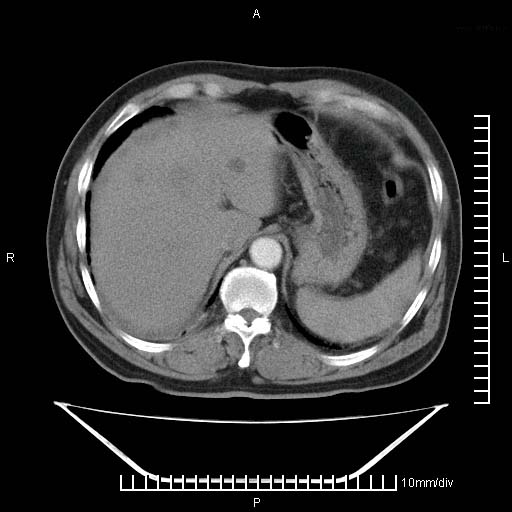

标题: CT25082:肝脏增强:男性,70岁 [打印本页]

标题: CT25082:肝脏增强:男性,70岁

患者以心脏疾病收住院,腹部无明显症状,b超查肝脏有占位。

肝内多发转移瘤,右下肺炎症并少量胸水。胃壁增厚建议胃镜,胰尾部“病变”为肠管。

1)肝脏多发性转移瘤(不排除胰尾癌转移所致可能)。2)腹水。3)右侧少量胸腔积液。

胰尾占位?结肠脾曲?

ct25082 结果:转移瘤

外院mr结果:胰尾恶性占位。

肝多发低密度灶;轻度强化,较水密度高,考虑转移,不排除肝脓肿